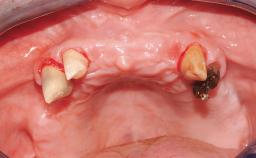

A 63-year-old male patient was referred for a consultation and treatment of partial edentulism in the maxilla. The patient presented with residual anterior teeth and declined a partial removable prosthesis. He reported that the maxillary posterior teeth had been extracted due to mobility and periodontal disease two months before the consultation. The patient’s chief complaint was that his residual maxillary teeth were mobile and that he was unable to chew. The patient’s desire was a stable and comfortable fixed maxillary rehabilitation. The patient was a light smoker (fewer than 10 cigarettes/ day), and his medical history was without significant findings. He was not on any regular medication at the time of consultation. The extraoral examination revealed a normal physiognomy with a correct distribution of the facial thirds. The patient presented a low lip line, and the transition line between teeth and soft tissues was not exposed during a forced smile.